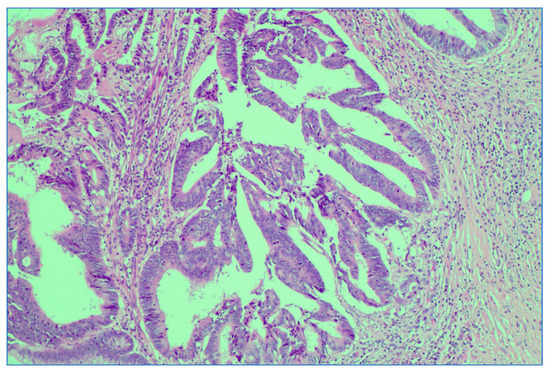

We analyzed the correlation between adjuvant chemotherapy treatment and histopathology bulletin results by using the Pearson correlation coefficient and applying the two-tailed significance t-test. The correlation between adjuvant chemotherapy and a pathological T staging greater than 2 (y)pT > 2 (Figure 6) and between adjuvant chemotherapy and a positive pathological N staging (y)pN > 0 was tested. Other risk factors from the histopathology report that were taken into account were the presence of lymphovascular invasion LVI+ (Figure 7), the presence of perineural invasion PNI+ (Figure 8), positive resection margins Postop+, or a histopathological grade greater than 1 Grade > 1.

Figure 6. Persistent rectal adenocarcinoma after neoadjuvant radiochemotherapy; ypT3 with invasion in subserosal adipose tissue. HE stain × 0.5 magnification.